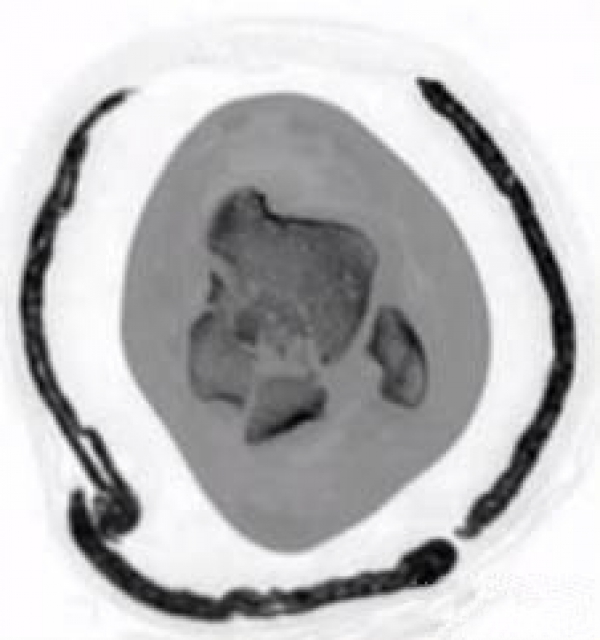

损伤主要位于以下几个主要部分:体、颈、后突、外突

当发生骨折脱位时,由于位移巨大,导致相应位移的血管损伤、最终导致距骨坏死,所以距骨骨折的分型常用Hawkins分型,距骨坏死率随分型严重程度逐渐增加。